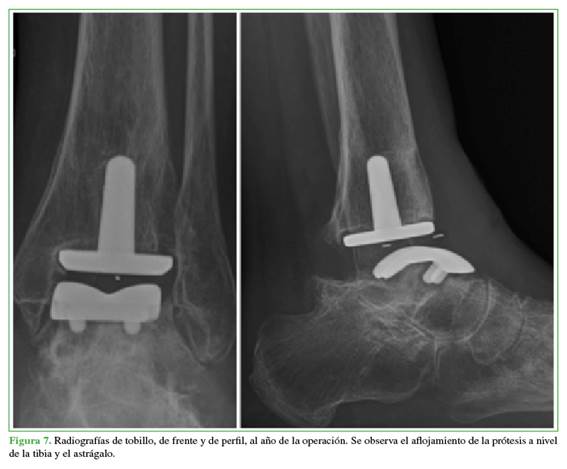

En las radiografías, se pudo observar una alteración de la estructura compatible con aflojamiento de la prótesis (Figura 7).

Ante la sospecha de aflojamiento séptico, debido a los antecedentes de infección, un defecto de cobertura durante nueve meses y la persistencia del dolor, al año y tres meses, se optó por una revisión en dos tiempos según los principios de Masquelet.